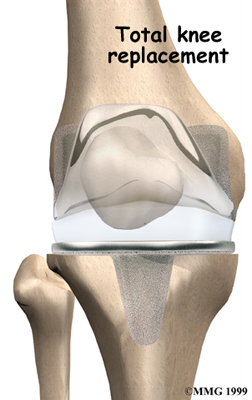

Artificial Knee Replacement

An artificial knee replacement is the ultimate solution for advanced knee OA.

Surgeons prefer not to put a new knee joint in patients younger than 60. This is because younger patients are generally more active and might put too much stress on the joint, causing it to loosen or even crack. A revision surgery to replace a damaged prosthesis is harder to do, has more possible complications, and is usually less successful than a first-time joint replacement surgery.

Related Document: FYZICAL New Orleans Guide to Artificial Joint Replacement of the Knee